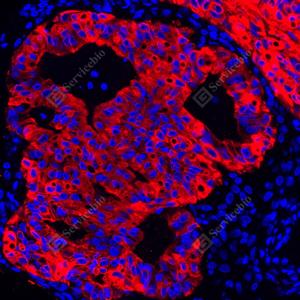

IF检测Cytokeratin 18蛋白(货号 GB15232)(红色). 样品: 人子宫内膜癌, 4%多聚甲醛 (货号G1101) 固定12-24小时. 抗原修复: 柠檬酸抗原修复液(干粉, pH 6.0) (G1201), 高压锅均匀喷气计时2分钟. 封闭: 3% BSA(货号GC305010)的PBS溶液, 室温孵育30分钟. —抗: 1: 1000稀释, 4℃ 孵育过夜. 二抗: Cy3标记山羊抗小鼠IgG (H+L) (货号GB21301), 1: 300稀释, 室温孵育1小时. |